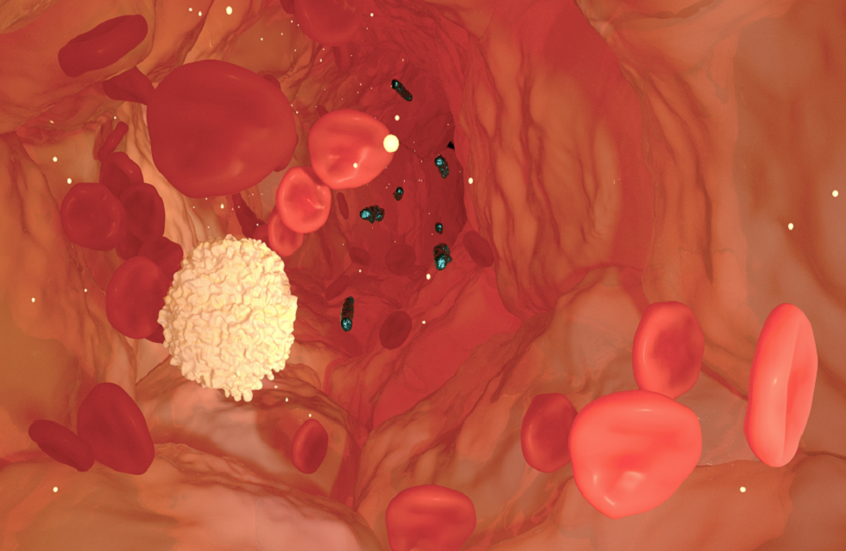

علاج محتمل جديد للإنتان

كشف باحثون من جامعة غريفيث عن نتائج علمية واعدة قد تمثل خطوة متقدمة في علاج الإنتان، بعد نجاح المرحلة الثانية من التجارب السريرية لدواء جديد، أُجريت في الصين.

ويعد الإنتان من الحالات الطبية الخطيرة التي تصيب ملايين المرضى في المستشفيات حول العالم سنويا، وينتج عن استجابة مناعية مفرطة للعدوى تؤدي إلى مهاجمة أنسجة الجسم وأعضائه، وقد تتطور إلى صدمة إنتانية وفشل متعدد في الأعضاء في حال عدم التشخيص والعلاج المبكرين.

وطوّر الباحثون دواء مرشحا لعلاج الإنتان يعرف باسم STC3141، وهو جزيء صغير قائم على الكربوهيدرات، وذلك بالتعاون بين البروفيسور مارك فون إيتزستين وفريقه من معهد الطب الحيوي وعلم السكريات في جامعة غريفيث، والبروفيسور كريستوفر باريش وفريقه من الجامعة الوطنية الأسترالية.

وأظهرت نتائج التجربة قدرة الدواء على الحد من الإنتان لدى البشر، بعد تحقيقه الأهداف الرئيسية للدراسة، بحسب ما أكده البروفيسور إيتزستين.

وأُعطي الدواء عبر الوريد بواسطة أنبوب صغير، بحيث يتدفق الدواء ببطء إلى الدم، حيث نجح في مواجهة ظاهرة إطلاق الجزيئات البيولوجية الكبيرة التي تحدث في الجسم خلال تطور الإنتان، ما يساهم في تقليل تلف الأعضاء وعكس آثاره. (عند حدوث الإنتان، يفرط جهاز المناعة في ردّة فعله، فيبدأ الجسم بإطلاق كميات كبيرة من مواد حيوية كبيرة الحجم إلى مجرى الدم. هذه المواد لا تكون ضارّة في الأصل، لكنها عندما تُطلق بكثرة وبلا ضبط تسبب التهابا شديدا وتلفا في الأعضاء).

وشملت المرحلة الثانية من التجربة، التي نفذتها شركة "غراند فارما" (Grand Pharma)، 180 مريضا مصابا بالإنتان، في ظل غياب علاج محدد لهذا المرض حتى الآن، ما يجعله من أبرز الاحتياجات الطبية غير الملبّاة عالميا.

وأفاد إيتزستين بأن الشركة تعتزم الانتقال إلى المرحلة الثالثة من التجارب السريرية لمواصلة تقييم فعالية العلاج الجديد وسلامته.

وأضاف: "نأمل أن يصبح هذا العلاج متاحا في الأسواق خلال السنوات القليلة المقبلة، بما قد يساهم في إنقاذ ملايين الأرواح".